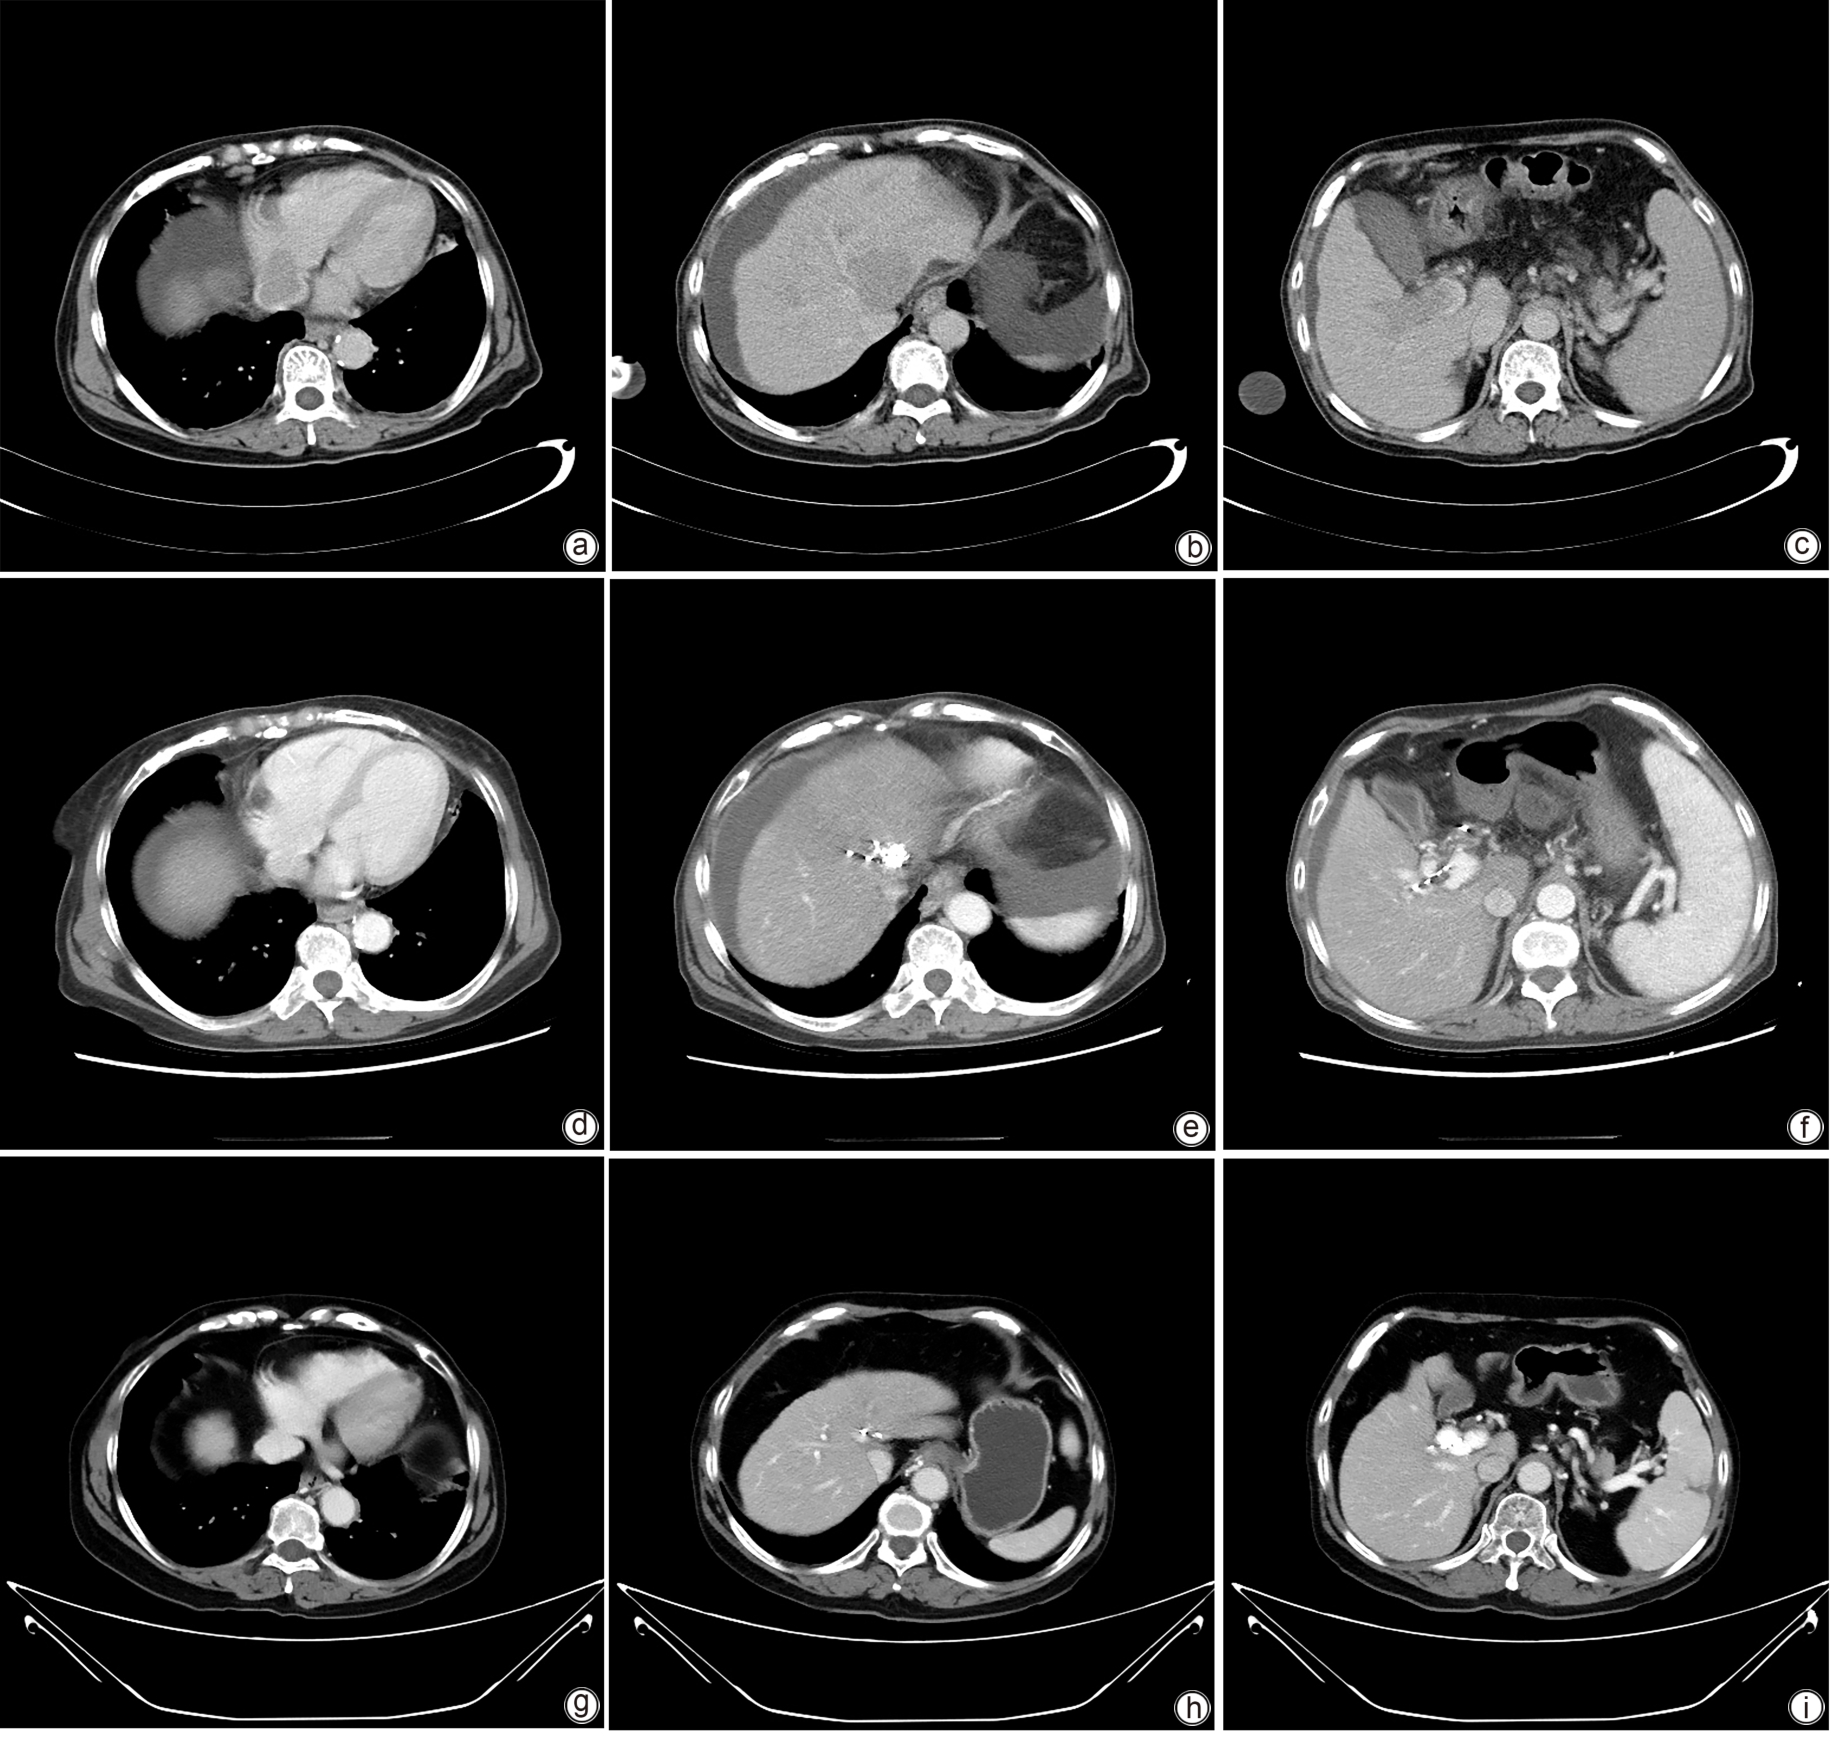

Large spontaneous splenorenal shunt embolization combined with anticoagulant therapy in treatment of portal vein thrombosis: A case report

Ju HUANG, Xiaoze WANG, Xuefeng LUO, Li YANG

2025, 41(8): 1639-1642. DOI: 10.12449/JCH250825

Abstract(513) HTML (178) PDF (3328KB)(71)

Abstract:

Portal vein thrombosis (PVT) is a common and severe complication in patients with liver cirrhosis, and alterations in portal hemodynamics are closely associated with the development of PVT. The presence of large spontaneous splenorenal shunt (SSRS) may lead to reductions in portal vein perfusion and blood flow velocity, which may compromise the anticoagulant effect on PVT. This article reports the treatment strategies of SSRS embolization combined with anticoagulant therapy that help to achieve complete recanalization of the portal vein; however, high-quality clinical studies are still needed to further validate and support the effectiveness of this strategy.